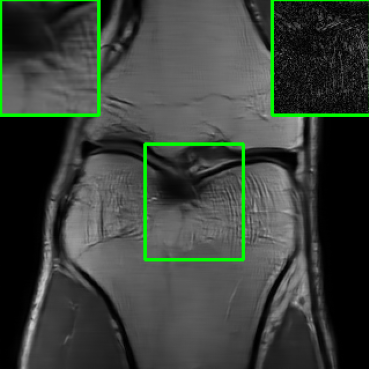

In addition to additive perturbations, the study presented in [32] underscores an additional potential source of instability that MoDL may face during testing. This source stems from changes in the measurement sampling rate, leading to perturbations in the sparsity of the sampling mask within [10]. Furthermore, in this paper, we consider another variation that MoDL could encounter during the testing phase, involving a shift in the k-space sampling locations within the matrix , resulting in the construction of a nonidentical forward operator for testing. For this case, , where . Figure 1 illustrates reconstructed images from the instabilities considered in this paper.

| PSNR = 29.8 dB | PSNR = 22.01 dB | PSNR = 20.28 dB | PSNR = 23.14 dB |

| (a) | (b) | (c) | (d) |

5.4 Visualizations

We now present visual samples from both the knee and brain datasets. Specifically, Figure 5 presents visual comparison of image reconstructions and their associated reconstruction errors within a closely examined region. Each image in the figure includes two inset panels in the top-left and top-right corners. The top-left inset panel, enclosed within a green bounding box, serves as a reference for the region of interest in the image. In contrast, the top-right inset panel depicts an error map in relation to the ground truth. Notably, our method stands out in its ability to capture the original image’s features, surpassing the performance of alternative methods (as also evident from the reported PSNR values). This visual comparison underscores the superior quality and accuracy of our approach in the robustification of the MRI image reconstruction task.